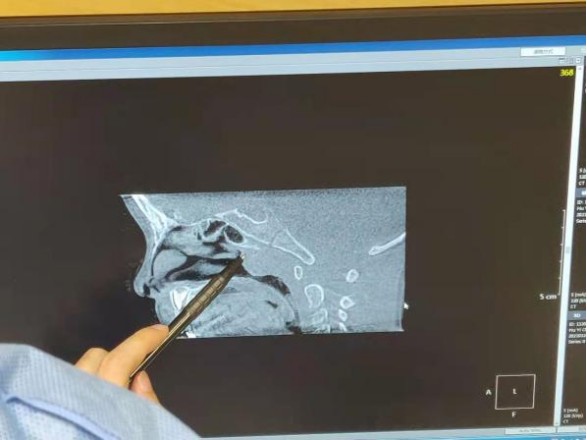

结合佳佳平时睡觉打呼噜的症状,贾主任为孩子做CBCT平扫,发现孩子是腺样体肥大,声导抗发现中耳负压,中耳炎影响听力。根据孩子的健康状况结合家长的意见,决定进行手术治疗。